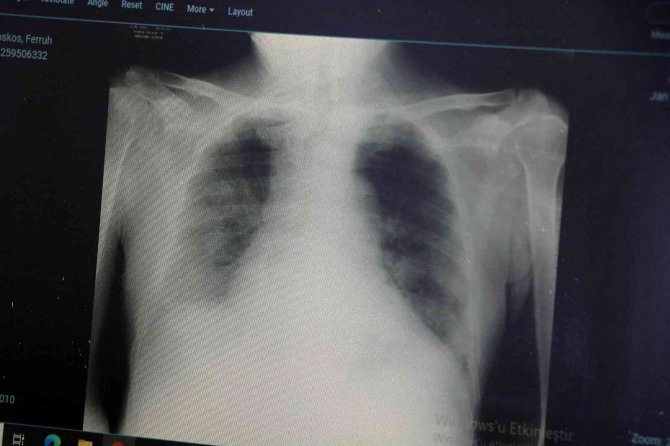

Son olarak varyantların akciğer tutulumları hakkında da bilgiler veren Dikmen, şunları söyledi:

"Delta varyantına yakalanan hastalarda akciğer tutulumunun daha fazla olduğunu görüyoruz. Omicron varyantına yakalanmış bir hastanın akciğer filmine baktığımızda ise deltaya göre çok az kaldığını görebiliyoruz. Bu da omicron geçiren bir hastanın, delta varyantına yakalanan bir hastaya göre daha rahat nefes aldığını gösteren bir durumdur."